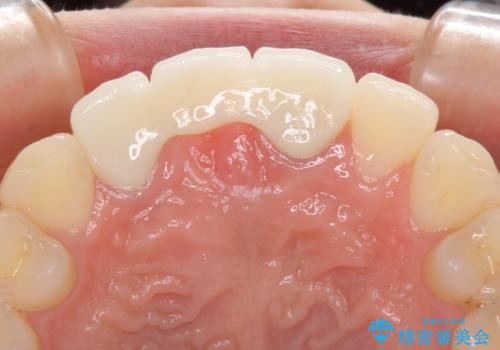

前院では、土台の金属を除去することは不可能であると言われたとのことでした。金属の土台が残っているとセラミックにグレーの金属色が透けて見えてしまうため、拡大鏡やマイクロスコープを用いて丁寧に除去し、天然歯の色に近いファイバーコアを植立することとしました。

また、歯とクラウンの境目が合っていない部分が多く、歯肉からの出血が認められました。